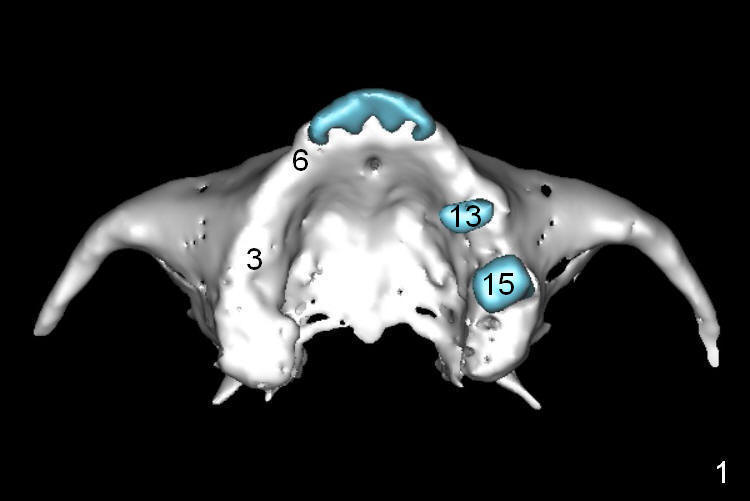

A 68-year-old lady has several missing teeth (Fig.1,2).  She has agreed to have an implant at the site of #3 (Fig.3) to stabilize an upper removable partial denture (RPD).  The latter will be more stable if an extra implant is placed at #6 (Fig.1,2,6).  There is enough bone to place implants at #4,5 (Fig.4,5).  Bone density at these sites is low.  Osteotomy should be underprep with bone condensation.  Edentulous space is high so long abutments are required (9 mm instead of 3 or 5 mm (regularly used)).  Angled abutments should be prepared.